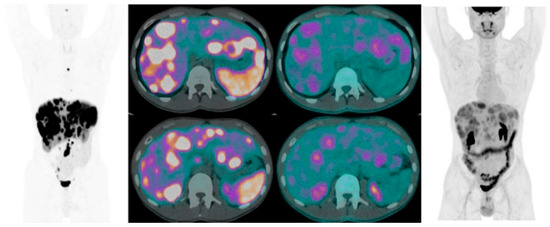

- Kayani, I.; Bomanji, J.B.; Groves, A.; Conway, G.; Gacinovic, S.; Win, T.; Dickson, J.; Caplin, M.; Ell, P.J. Functional Imaging Of Neuroendocrine Tumors With Combined 68Ga-DOTATATE (Dota-DPhe1,Tyr3-octreotate) and [18F]FDG PET/CT. Cancer 2008, 112, 2447–2455. [Google Scholar] [CrossRef] [PubMed]

| Functional Imaging Of Neuroendocrine Tumors With Combined 68Ga-DOTA-TATE (Dota-DPhe1,Tyr3-octreotate) and [18F]FDG PET/CT | The role of the 2 tracer may be complementary in mapping patients with metastatic tumors. | [42] |